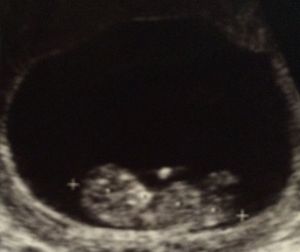

We take great delight in God’s blessings to us – even when His blessings come in the form of a very unexpected surprise …

“Behold, children are a heritage from the Lord, the fruit of the womb a reward. Like arrows in the hand of a warrior are the children of one’s youth. Blessed is the man who fills his quiver with them…” Psalm 127:3:5a

“Your wife will be like a fruitful vine within your house; your children will be like olive shoots around your table. Behold, thus shall the man be blessed who fears the Lord.” Psalm 128:3-4